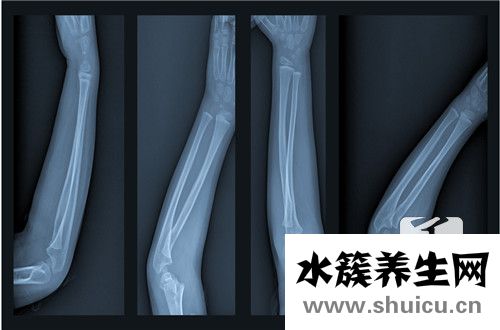

右撓骨遠(yuǎn)端骨折在生活當(dāng)中比較常見(jiàn),占總的骨折大約1/10左右.多見(jiàn)一些中老年人,尤其是老年女性,因?yàn)楣琴|(zhì)疏松的原因,很可能發(fā)生這個(gè)部位發(fā)生骨折,相對(duì)來(lái)說(shuō)是比較嚴(yán)重的,因?yàn)榘l(fā)生骨折以后會(huì)導(dǎo)致脹痛等現(xiàn)...